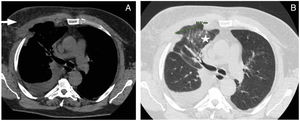

Durante su estancia en área de hospitalización, empeoramiento de la situación clínica con episodios de hemoptisis intermitente, decidiéndose realizar una angiotomografía computarizada de tórax (angio-TC) observándose rotura a nivel del 4.° al 7.° cartílago costal derecho, diátesis de los mismos, provocando la herniación de parénquima pulmonar por dicha zona junto con engrosamiento de la musculatura pectoral derecha, edema del tejido subcutáneo e infiltrados alveolares parcheados relacionados con pequeña área de sangrado a nivel del parénquima pulmonar (fig. 2).

A) Corte sagital angio-TC de tórax donde se objetiva mínimo derrame pleural derecho, asociado con defecto de continuidad a nivel de arcos costales y edematización de tejido muscular y subcutáneo (flecha). B) Corte sagital angio-TC de tórax observando la herniación del parénquima pulmonar junto con infiltrado asociado (estrella).